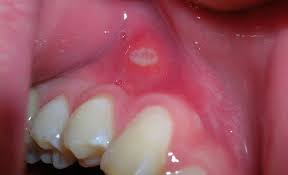

Not like oh yeah i stutter sometimes more the king's speech kind of stuttering. What you need to know about oral cancer Cancer is defined as the uncontrollable growth of cells that invade and cause damage to surrounding tissue. There are three types of biopsies, according to the american cancer society. In many cases, navigating a cancer diagnosis and understanding treatment plans can be. Signs and symptoms of cancer depend on where the cancer is, how big it is, and how much it affects nearby organs or tissues. Cancer that starts in the middle part of the throat is called oropharyngeal cancer. These cells can develop from oral hpv. Oral cancer often starts as a tiny, unnoticed white or red spot or sore anywhere in the mouth. Cancer that starts in the head and neck area can have many different names depending on. Oral cancer affects both men and women, especially those who are 40+. Cancer that starts in the mouth is called oral cavity cancer. What you should know about oral cancer.

What Does Oral Cancer Look Like Images And Symptoms

What Does Oral Cancer Look Like Images And Symptoms from post.medicalnewstoday.com

If symptoms persist for several weeks or months, it is important to see your doctor so that, if oral cancer is present, it may be diagnosed as soon as possible. If you have oropharyngeal cancer, cancer cells form in the middle of the throat, including the tongue, tonsils, and pharynx walls. Tongue cancer is a type of cancer that starts in the cells of the tongue, and can cause lesions or tumors on your tongue. Not like oh yeah i stutter sometimes more the king's speech kind of stuttering. While the only chance to cure is surgery. You have a right to be heard. Signs and symptoms of cancer depend on where the cancer is, how big it is, and how much it affects nearby organs or tissues. Whether you're the giver or receiver of oral sex, you can contract and/or spread stis. There are three types of biopsies, according to the american cancer society. Not all patients have pain or irritation. Many symptoms caused by oral tumors may be due to other, less serious conditions or other cancers. Our cancer doctors use a variety of diagnostic tests to evaluate oral cancer and develop an individualized treatment plan. Many are just risk factors that compromise the state of your oral health, encouraging the development of precancerous cells.